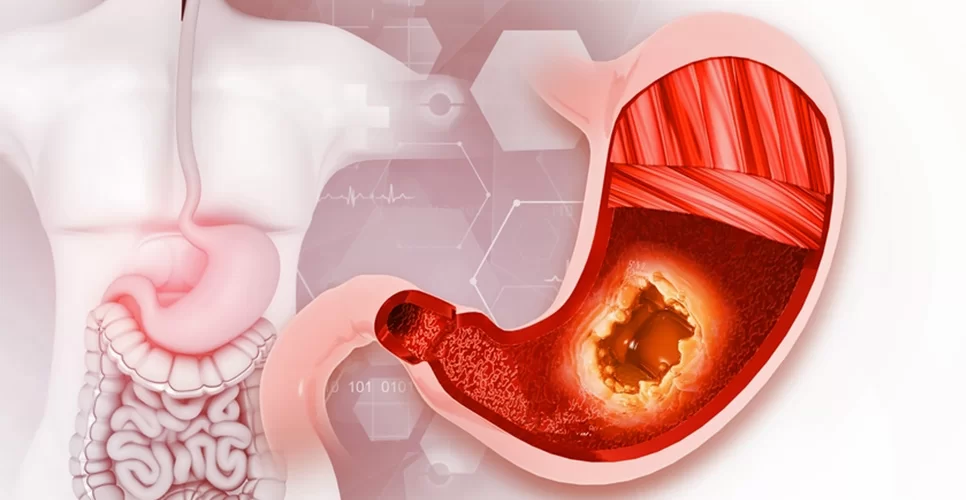

Midenizde yanma, kazınma, ağrı ya da bulantı mı hissediyorsunuz? Bu belirtiler mide ülserinin habercisi olabilir. Modern tıbbın sunduğu tedavilerin yanı sıra, bitkisel desteklerle mide ülseri şikayetlerini hafifletmek mümkün! İşte mide ülserine iyi gelen doğal yöntemler ve şifalı bitkiler…